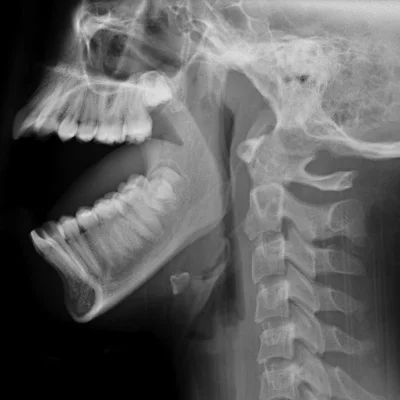

Dental X-Ray for Oral and Maxillofacial Evaluation

Dental X-rays are essential for diagnosing conditions that aren’t visible during a routine dental exam. At Alpha Imaging, we provide high-resolution dental radiography for

Jaw and TMJ Imaging

Diagnosing joint dysfunction or trauma.